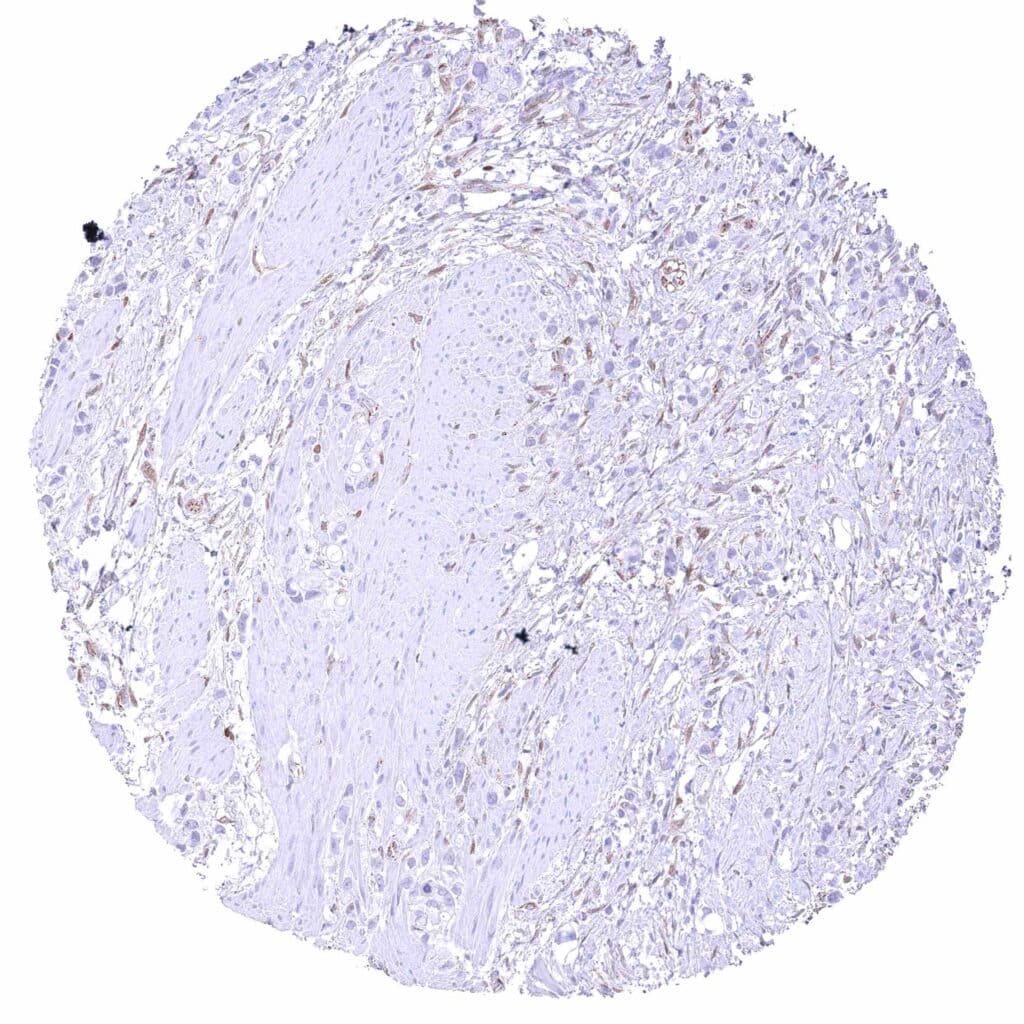

Skin – Malignant melanoma with strong cytoplasmic and nuclear β-Catenin staining of tumor cells.